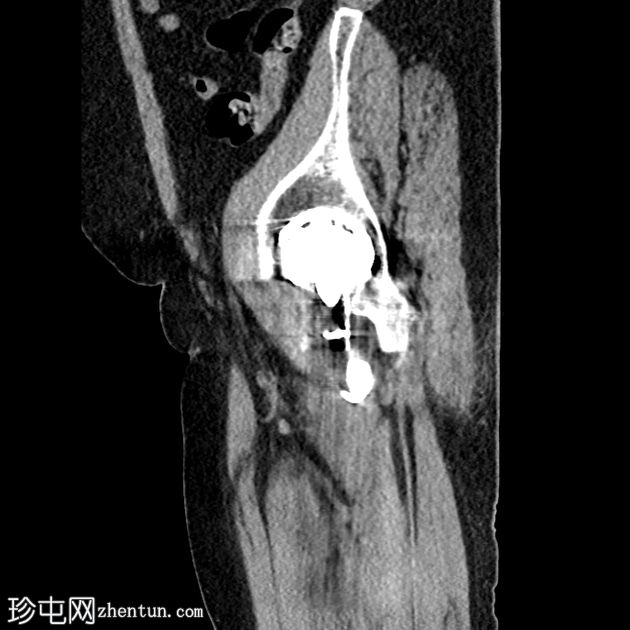

冠状位片

平扫

左侧全髋关节置换术。大转子基底部可见轻微移位的假体周围骨折。

大转子滑囊积液,可见脂肪-液体平面。